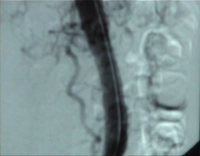

Video clip: SMA occlusion close to its origin with occlusion of the celiac trunk